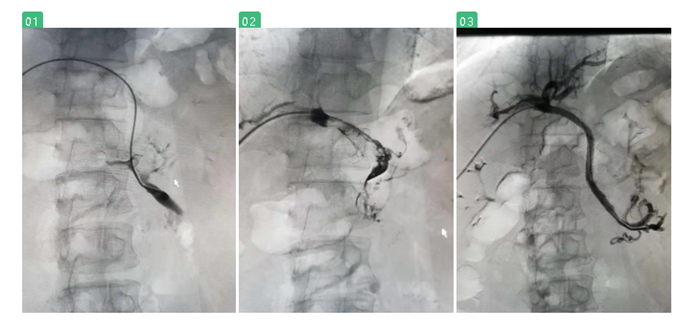

在陸煒的指導下,血管外科診療組長程國兵副主任醫(yī)師為江先生施行“經(jīng)皮肝穿刺門靜脈、腸系膜上靜脈造影+Angiojet吸栓+支架植入球囊擴張術”。

經(jīng)過季肋部穿刺至門靜脈時,發(fā)現(xiàn)江先生的門靜脈及腸系膜上靜脈已完全閉塞,程國兵巧妙地引入導絲、放入導管,一點點清除門靜脈血栓,最后,成功放入支架。

術中復查造影,顯示支架定位準確,展開良好,腸系膜上靜脈及門靜脈主干血流通暢。

圖一、二:血管閉塞,充滿血栓 圖三:血栓清除,恢復血流